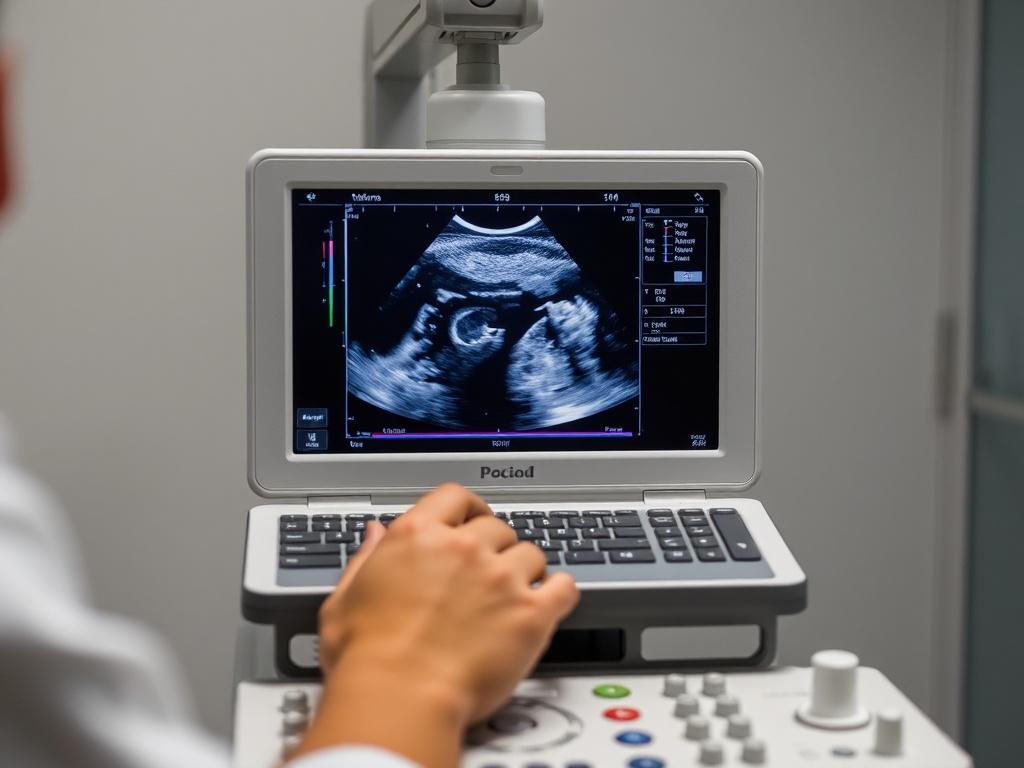

УЗИ — это исследование с помощью звуковых волн высокой частоты. Аппарат посылает сигнал через датчик, волны проходят через ткани, отражаются от границ органов и возвращаются обратно. На основе этих отражений формируется изображение. Процесс происходит мгновенно, изображение обновляется в реальном времени, поэтому врач не только фиксирует состояние органа, но и оценивает его движение и кровоток. На сайте https://medcenter-stomalux.ru/services_cat/uzi-diagnostika/ можно получить больше информации про УЗИ-диагностику.

- Контроль беременности: скрининг на ранних сроках, оценка развития плода, положение плаценты.

УЗИ показывает форму, размер и структуру органа. Врач отмечает эхогенность, контуры и наличие включений — кист, камней, жидкостных полостей. В протоколе обычно указывают размеры, однородность ткани и заключение с рекомендациями.

Протокол читается так: сначала описательная часть — что увидел врач, затем измерения, потом заключение. Для пациента ключевое — заключение и рекомендации. Если в заключении есть сомнения, врач может предложить дообследование: КТ, МРТ или лабораторные анализы.